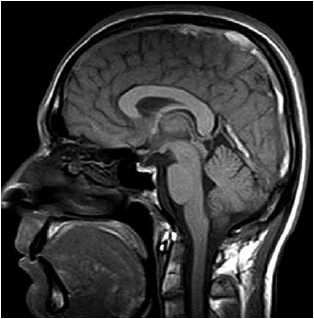

Mulher de 23 anos com 14 semanas de gestação relata quadro de cefaleia holocraniana há uma semana, que vem piorando de intensidade. A dor de cabeça piora à noite e causa visão embaçada. O exame clínico é normal e não há déficit neurológico focal, nem rigidez de nuca. Exames séricos são normais. A ressonância magnética T1 sagital realizada é mostrada a seguir:

(Arquivo pessoal; imagem usada com autorização)

Constitui a principal hipótese que justifica o quadro descrito: